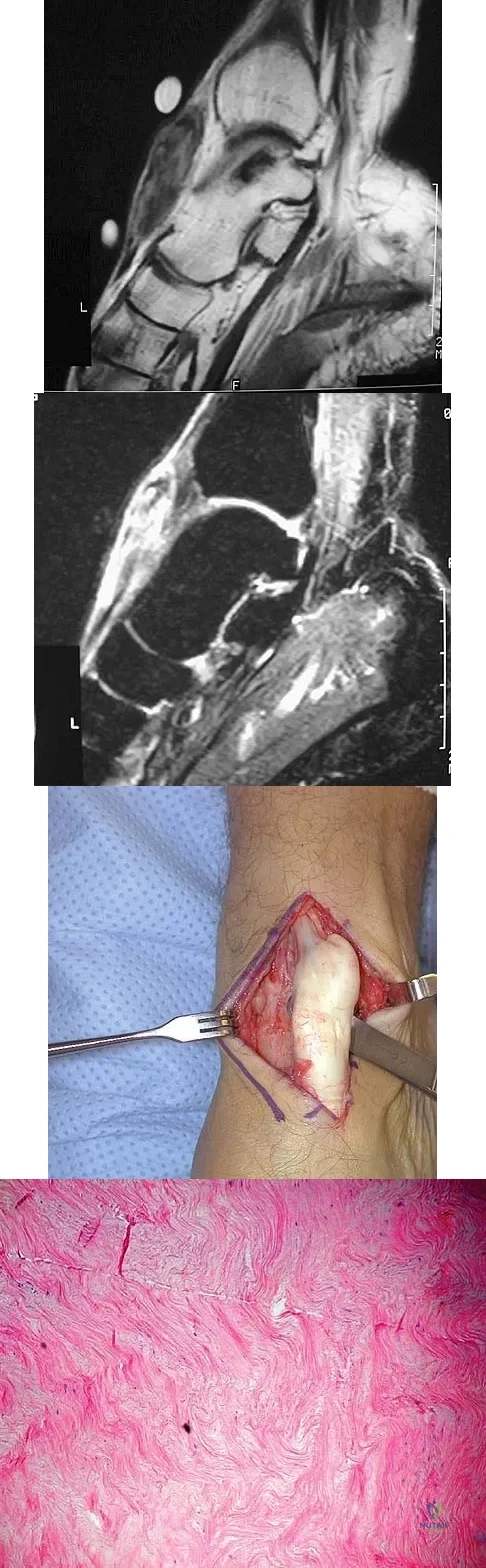

A 51-year-old male truck driver has had progressive left hip pain for more than 2 years, and he reports that the pain has become severe in the past 9 months. He is now unable to work because of the pain. Examination reveals that range of motion of the hip is limited to 95 degrees of flexion, 0 degrees of internal rotation, and 20 degrees of external rotation. The plain radiograph, MRI scan, and intraoperative gross photographs are shown in Figures 9a through 9d. Management should consist of

A 16-year-old boy has had left knee pain and swelling after sustaining a minor twisting injury while playing basketball 2 weeks ago. Figures 5a through 5e show the radiograph, MRI scans, and biopsy specimens. What is the most likely diagnosis?

A 65-year-old woman has had chronic aching discomfort involving her elbow for the past 6 months. Radiographs and a biopsy specimen are shown in Figures 38a through 38c. What is the most likely diagnosis?

A 40-year-old man has a palpable mass over the dorsum of the ankle. He reports no history of direct trauma but notes that he sustained a laceration to the middle of his leg 6 weeks ago. Examination reveals a 4-cm x 1-cm mass. T1- and T2-weighted MRI scans are shown in Figures 12a and 12b. An intraoperative photograph and biopsy specimen are shown in Figures 12c and 12d. What is the most likely diagnosis?